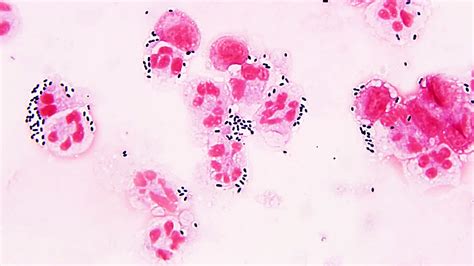

Alright, let’s get down to the nitty-gritty of Streptococcus bacteria . These guys are Gram-positive, which basically means when you look at them under a microscope after a special staining process, they show up a certain color and have a specific type of cell wall. They’re also cocci, meaning they’re spherical or oval-shaped. What’s super distinctive about them is how they arrange themselves – they typically form chains or pairs, kind of like little beads on a string, which is where the name ‘Streptococcus’ comes from (from the Greek word ‘streptos’ meaning twisted or chain-like). This arrangement is a big clue for microbiologists when they’re trying to identify them. But don’t let their simple shape fool you; these bacteria are incredibly diverse. They can be found all over the place – on our skin, in our mouths, and in our digestive tracts – and many of them are actually harmless, even beneficial, part of our natural flora. They’re like tiny tenants living on and in us! However, some strains are opportunistic pathogens, meaning they can cause trouble when the conditions are right, like if our immune system is weakened or if they find their way into parts of the body where they shouldn’t be. This duality is what makes studying Streptococcus so interesting and crucial for public health. The sheer variety within the Streptococcus genus means that not all strains are created equal when it comes to causing disease. Some are incredibly virulent, meaning they can cause severe illness quickly, while others are much more benign. Scientists classify these bacteria using different methods, including how they look under the microscope, their biochemical properties, and importantly, their hemolytic activity – that is, whether and how they break down red blood cells in a lab setting. This classification system helps doctors and researchers distinguish between the different types and predict their potential impact on human health.

Now, let’s break down the different types of Streptococcus bacteria , because not all Strep are the same. It’s a bit like saying ‘dog’ – there are poodles, bulldogs, and beagles, all dogs, but very different! Scientists have developed ways to classify these bacteria, and one of the most common methods is based on how they affect red blood cells in a petri dish. This is called hemolysis. You’ve got:

• Alpha-hemolytic (α-hemolytic) streptococci : These guys cause partial lysis of red blood cells. They create a greenish discoloration around their colonies on blood agar. A well-known example here is Streptococcus pneumoniae , which is a major cause of pneumonia, ear infections, and meningitis. So, even partial hemolysis doesn’t mean they’re harmless!

• Beta-hemolytic (β-hemolytic) streptococci : These are the ones that cause complete lysis of red blood cells, creating clear zones around their colonies. This group includes some of the most notorious pathogens, like Streptococcus pyogenes (Group A Strep) and Streptococcus agalactiae (Group B Strep). We’ll talk more about these baddies soon.

• Gamma-hemolytic (γ-hemolytic) streptococci : These don’t cause any hemolysis at all. They’re often found in the gut and are generally considered less pathogenic, though they can cause infections in certain circumstances, especially in people with weakened immune systems.